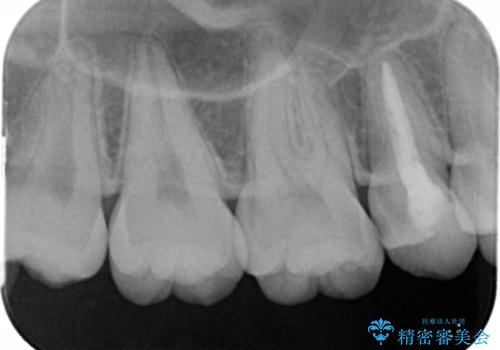

- 右上の5番目の歯の神経の治療のやり直しとセラミック治療を行いました。

術前ですでに変色が始まっているのがわかります。

術前はCRで蓋をしてあるだけでしたが、クラウンにした方が破折のリスクが少なくなります。また、根の治療がしてある歯ですが、クラウンにした方が封鎖は確実なため、長期的には有利です。また、変色の進行も外からは見えなくなりますので審美的です。